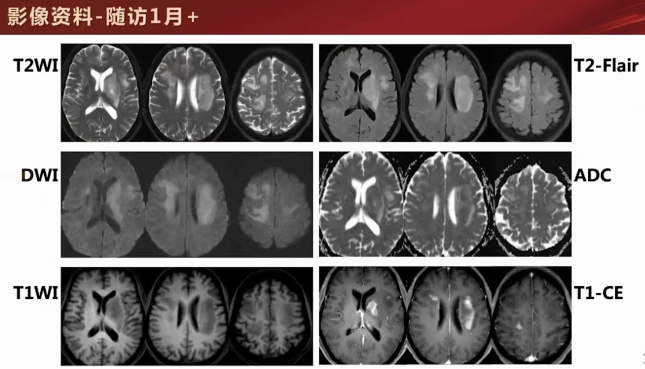

2) 影像学检查

一月后:病灶呈明显团块样,效应和水肿加重,出现轻度握拳征、局部凹陷脐凹征,增强后左侧基底节区与右侧额顶叶皮层线样结节样强化。